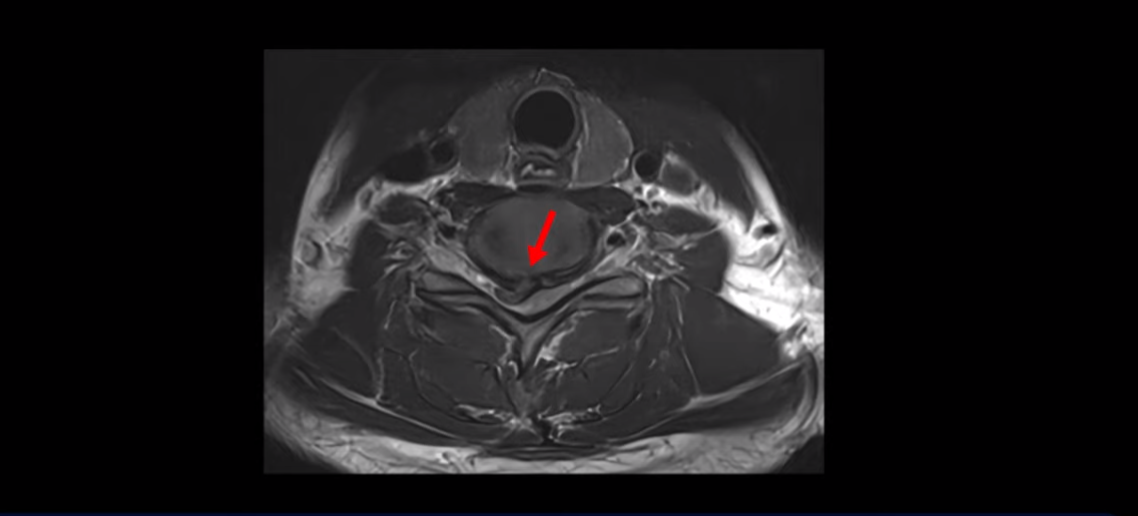

이분 목 MRI를 보면 6번, 7번 디스크에 매우 심한 디스크 파열이 있습니다.

이렇게 심하게 척수 신경을 누르니까 신경 손상이 생기고 척수증 증상이 발생하는 겁니다.